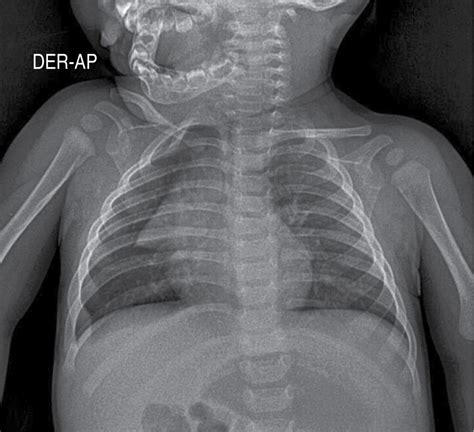

En su artículo, los autores señalan que se trata de un fenómeno extremadamente raro que puede ocurrir con una frecuencia de un caso por cada 500.000 nacimientos. Los exámenes como la tomografía computarizada abdominal y las imágenes de rayos X son cruciales para detectar estas anomalías, registrando en el cuerpo del bebé una masa con el contorno óseo de una columna vertebral y extremidades en pleno desarrollo.